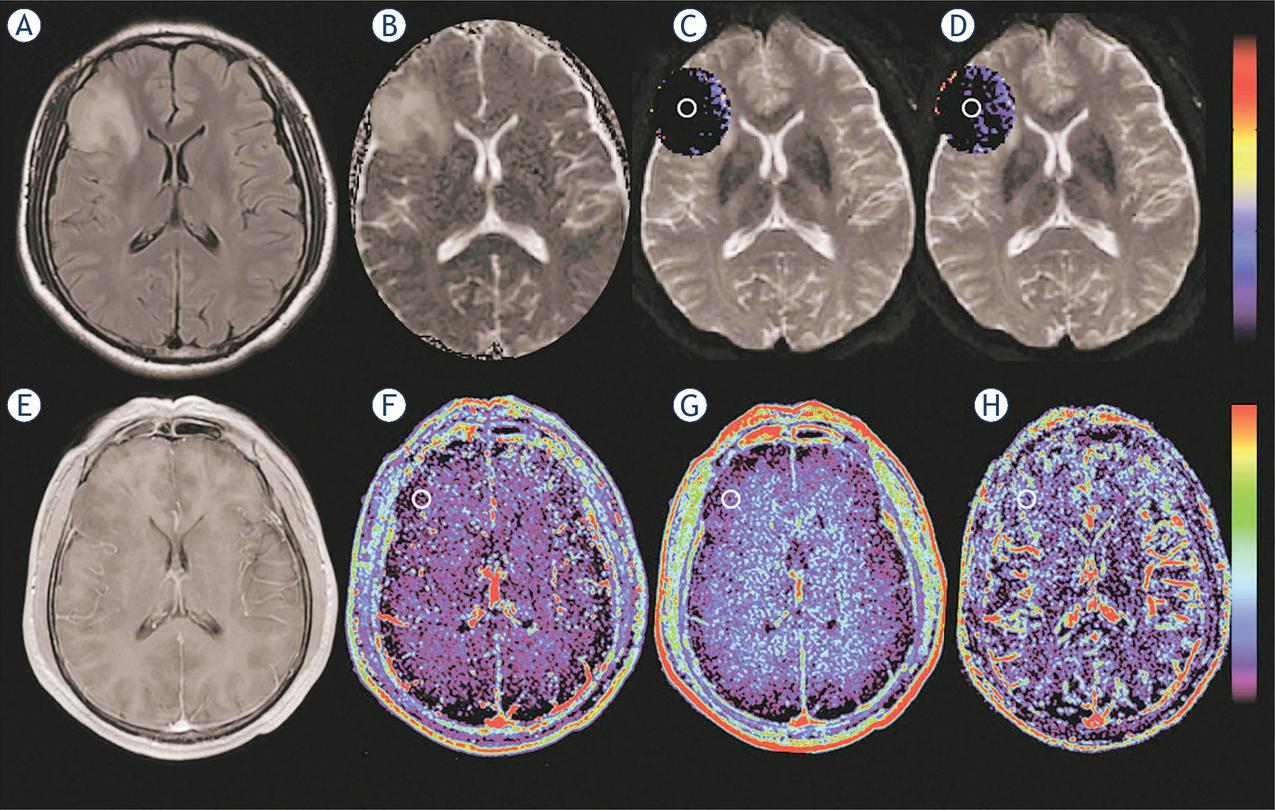

Figure 1